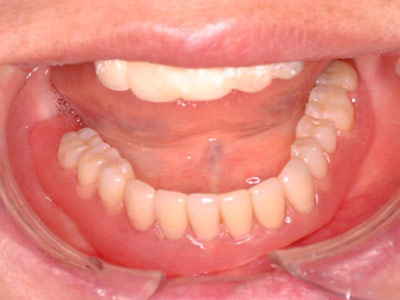

写真は、抜歯後の口腔内の写真です。見るからに、骨が少なく、陥凹してしまっていました。 -

特に下顎の臼歯部で、歯が抜けた後に顎の骨の吸収とともに、頬の側の動く粘膜が内側に押し寄せて、固い歯肉が狭くなってしまうことがあります。また、上顎の前歯部でも、歯が抜けた後に、外側の(唇側の)顎骨が吸収されてしまうために、歯肉が凹んだ状態になってしまい、歯肉に厚みを持たせることが必要になることがあります。

そのために、必要に応じて、狭くなってしまった固い歯肉の幅を、インプラントの直径よりもひと回り大きく拡げる手術を行ったり、薄くなってしまった歯肉の厚みを増加させる手術を行います。-